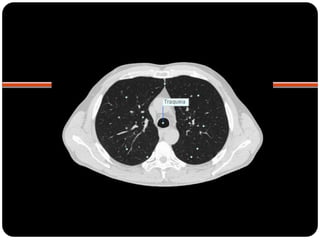

TRAQUÉIA

Vias aéreas

 Anéis cartilaginosos em forma de C;

 Membrana traqueal posterior: músculo e tecido

conjuntivo;

 Identações na parede lateral esquerda da

traquéia distal  arco aórtico;

 12cm;

 Transparência cilíndrica da cartilagem cricóide

até os brônquios principais;

 Normal ligeiro desvio da traquéia para a direita;

 Linha paratraqueal direita (interface do LSD

com parede lateral direita da traquéia): não

deve ultrapassar 4mm ;

 Parede paratraqueal esquerda circundada por

tecido adiposo e vasos mediastinais 

normalmente não é vista na radiografia;